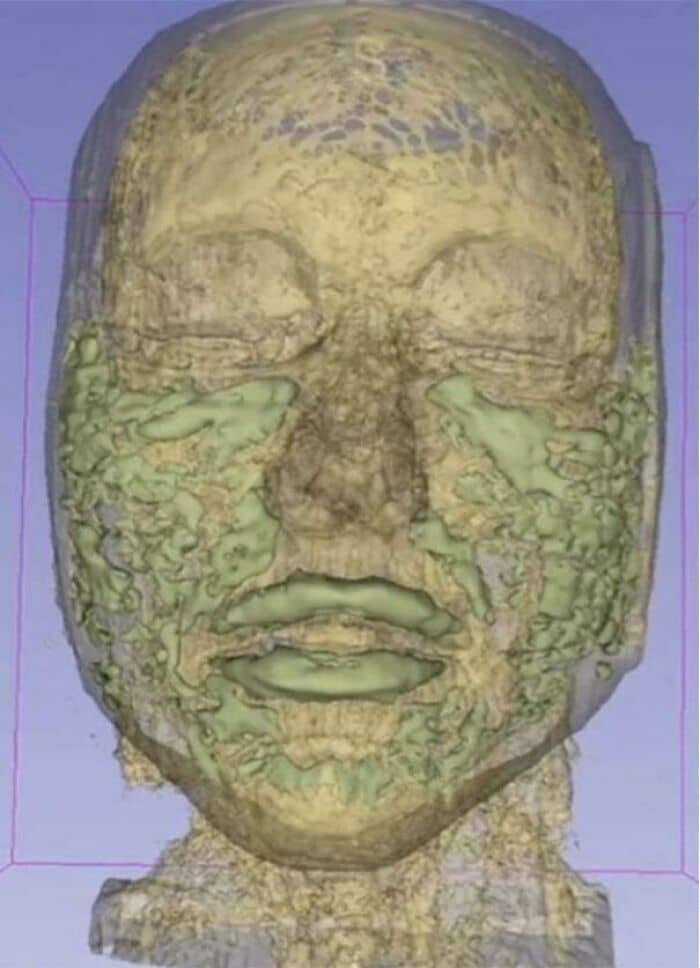

#41 Scan Of A Face With Years Of Dermal Filler Build Up